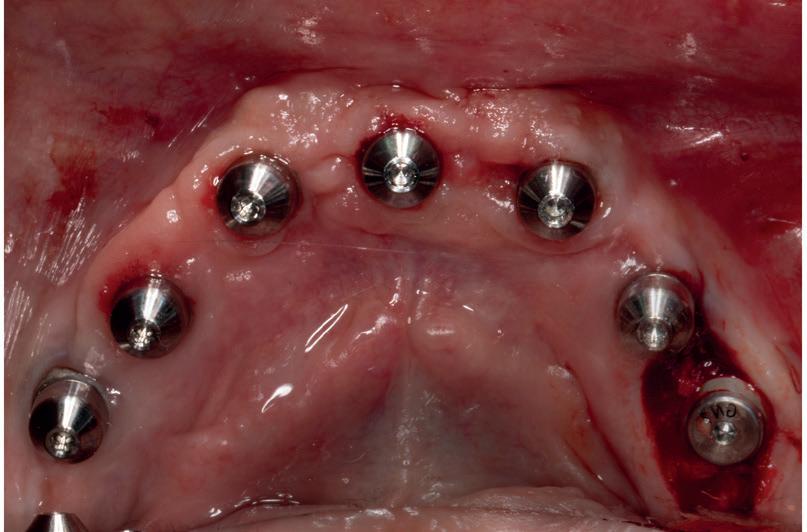

RECONFIGURAREA suportului osos implantar. În cazul prezentat, după ani de terapie ortodontică incorect executată, dezvoltarea dentară a pacientului a complicat obținerea unui zâmbet estetic. S-a reanalizat și s-a optat pentru abordare interdisciplinară care cuprinde chirurgia parodontală, un al doilea tratament

ortodontic și protetica pentru a oferi îngrijirea comprehensivă.